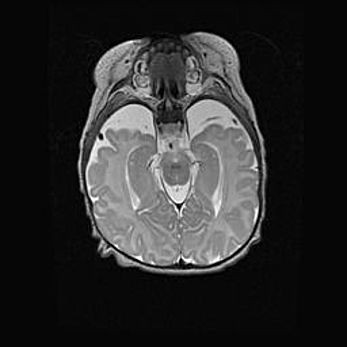

Аномалия Денди-Уокера. Признаки гипоплазии мозолистого тела.

Возраст: 5 месяцев 3 дня

Вес: 5550 г

Пол: мужской

Окружность головы: 39 см

Срок гестации: 40 недель

Аномалия Денди-Уокера – это порок развития головного мозга, для которого характерна триада симптомов: гипотрофия или аплазия червя мозжечка и/или полушарий мозжечка, расширение четвёртого желудочка с формированием ликворной кисты задней черепной ямки, гипертензионная гидроцефалия различной степени.

Гипоплазия мозолистого тела относится к дефектам внутриутробного этапа развития мозговой ткани, возникающим в процессе закладки структур головного мозга, что происходит на начальных этапах развития эмбриона.